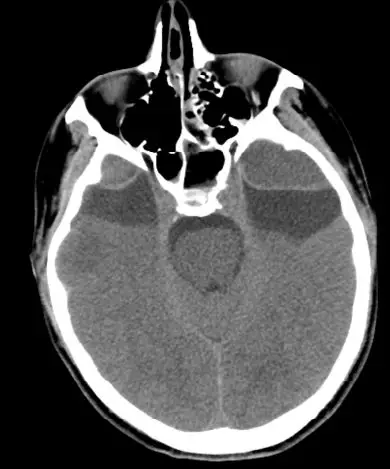

25岁男性患者,有双侧颞部蛛网膜囊肿,因醉驾而发生车祸。入院时GCS评分为15分,体格检查未见阳性体征;头颅CT和MRI提示双侧颞部蛛网膜囊肿的前端各有一颞部硬膜外血肿。左颞蛛网膜囊肿为4.8×5.4cm,右颞囊肿为3.1×3.7cm。左侧颞部EDH最大厚度3cm,右侧2.2cm;同时伴有横向的颞骨骨折(图1)。给予患者保守治疗。随后的CT复查显示EDH稳定(图2)。出院后3周,复查头颅CT显示,EDH明显吸收(图3)。

图1. 双侧颞部蛛网膜囊肿前端发生创伤性硬膜外血肿。A.头颅CT;B.MRI-T2加权像。